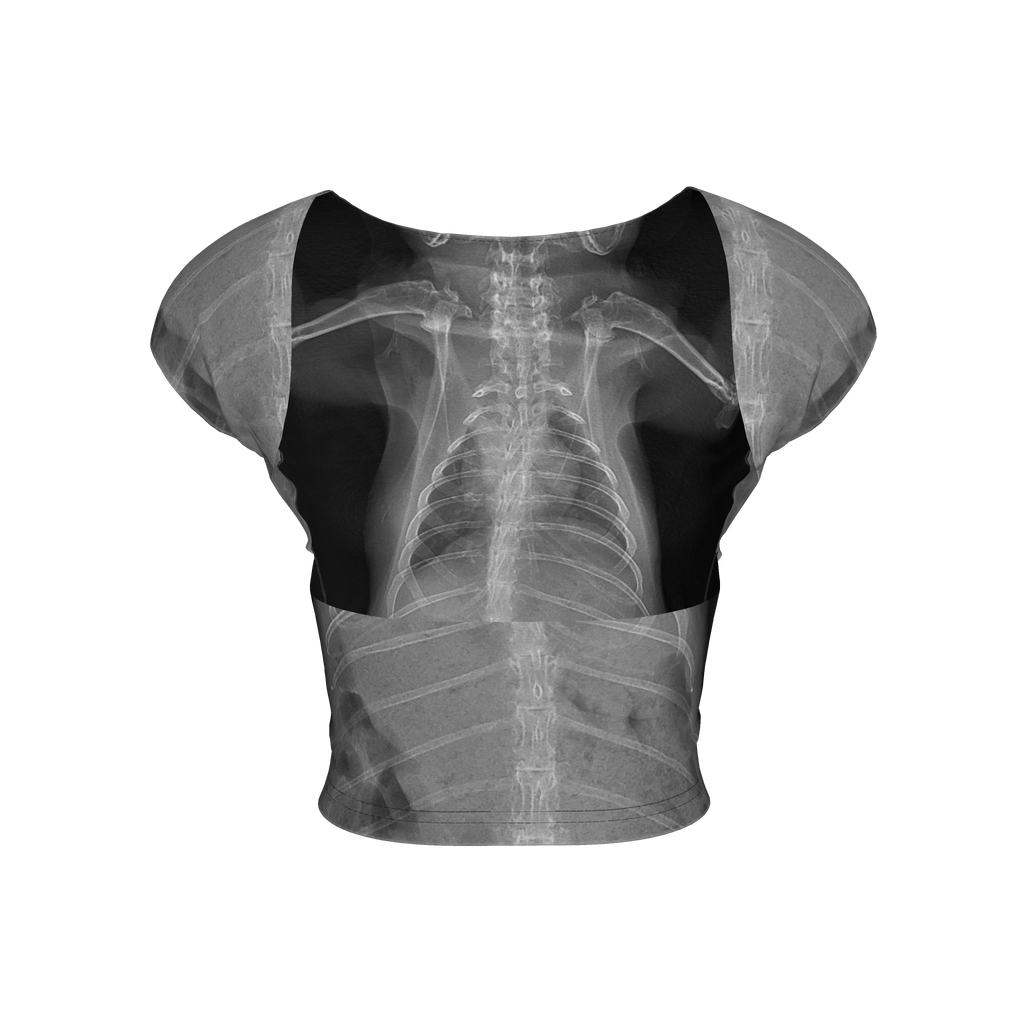

Toll of Love Backless Top

My pet rabbit had a health crisis earlier this year and needed intensive care. It was a long night at the hospital, but she is doing well. Her X-rays were a beautiful thing to come out of a horrible night and I made this outfit to transform those memories into something beautiful.